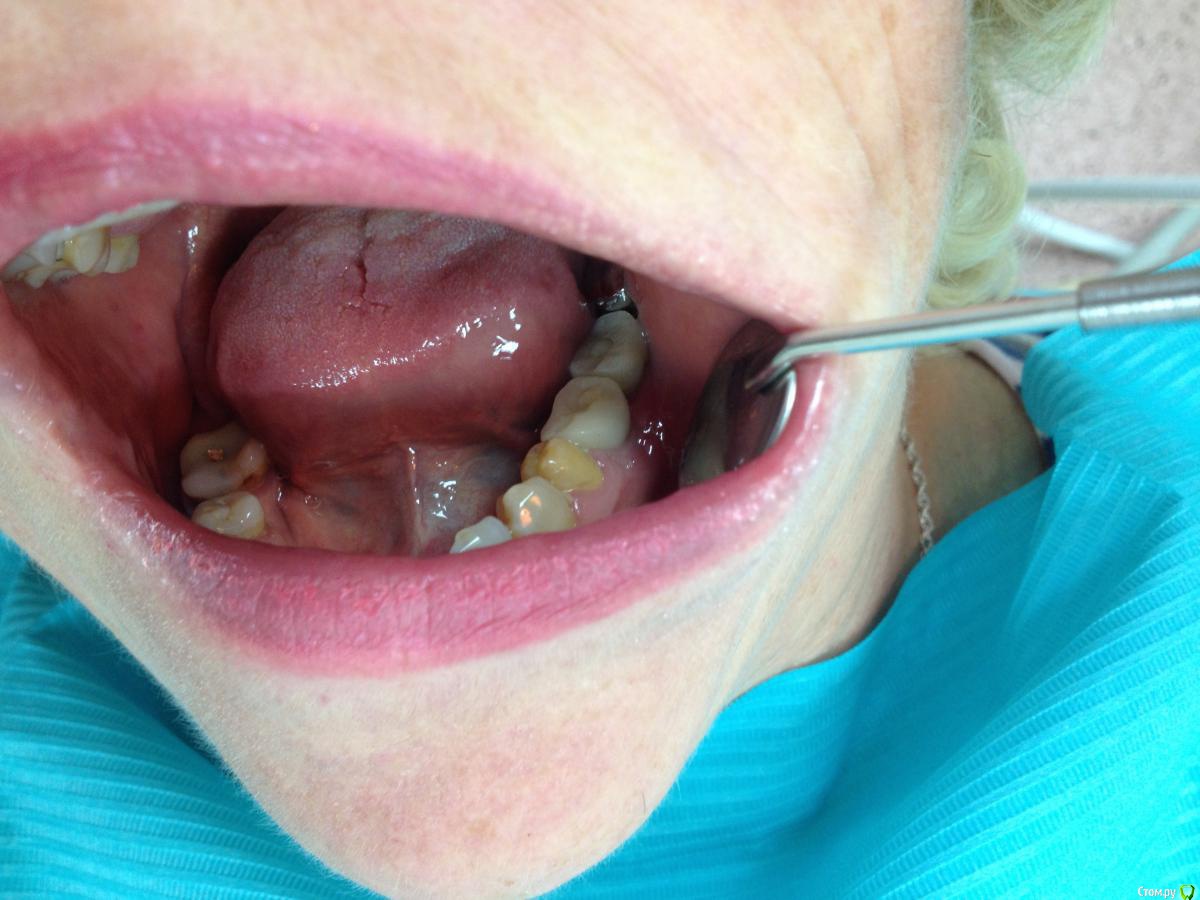

Shakirbura Опубликовано 1 декабря, 2016 Автор Поделиться Опубликовано 1 декабря, 2016 Изготовили временные коронки на 3 месяца. Вроде ситуация нормализовалась. Карманов нету.Всем спасибо за рекомендации! Отдельное спасибо Ст@се! 11 Ссылка на комментарий